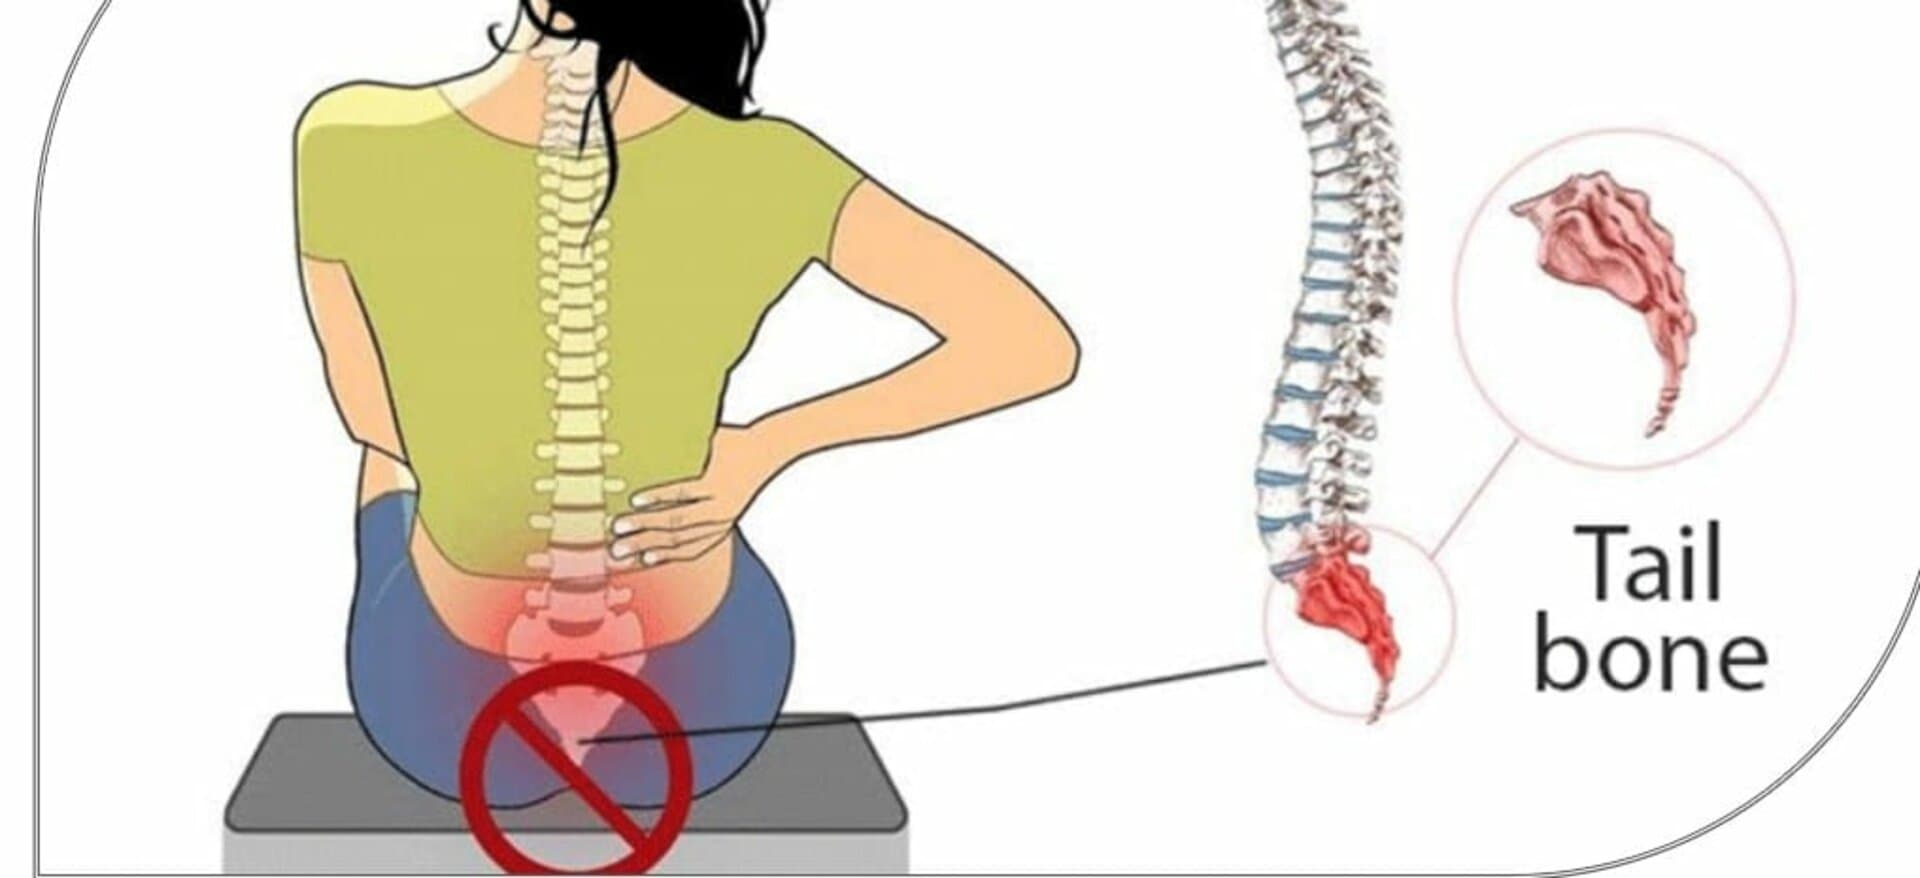

ألم العصعص | عجز الذنب

ألم العصعص تعريفه اسبابه اعراضه وعلاجه